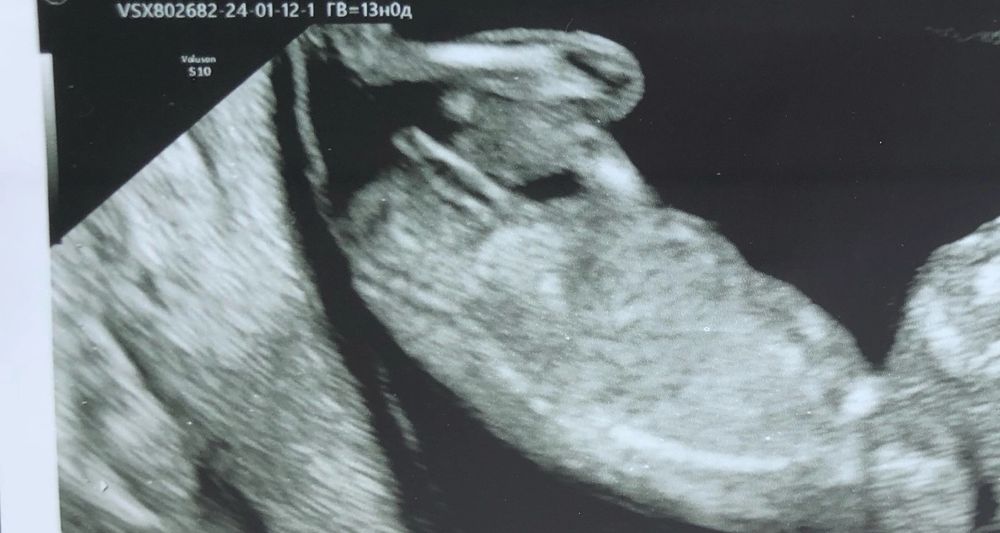

Девочки подружка прислала. Это же очевидно девочка, неужели так рано видно уже 13 недель и чётко пол

Ну да, на девочку похоже) Половой бугорок отчётливо виден и идёт параллельно позвоночнику. Через пару недель пол уже будет почти не различим, недель до 18-20. А в 12-13 самое оно определить. Ну, если грамотный узист, конечно))

Мне в 12 недель сказали пол. А чем вам здесь очевидно?) я б вот никогда не сказала кто тут по этому фото

Мария, ну тут половой бугорок чётко видно, врачи то в них разбираются. Могут, конечно и ошибиться на таком сроке. Мне на 12, 16, 20 и 26 неделях всегда одно и то же говорили, без сомнений. А иногда малыш прячется)